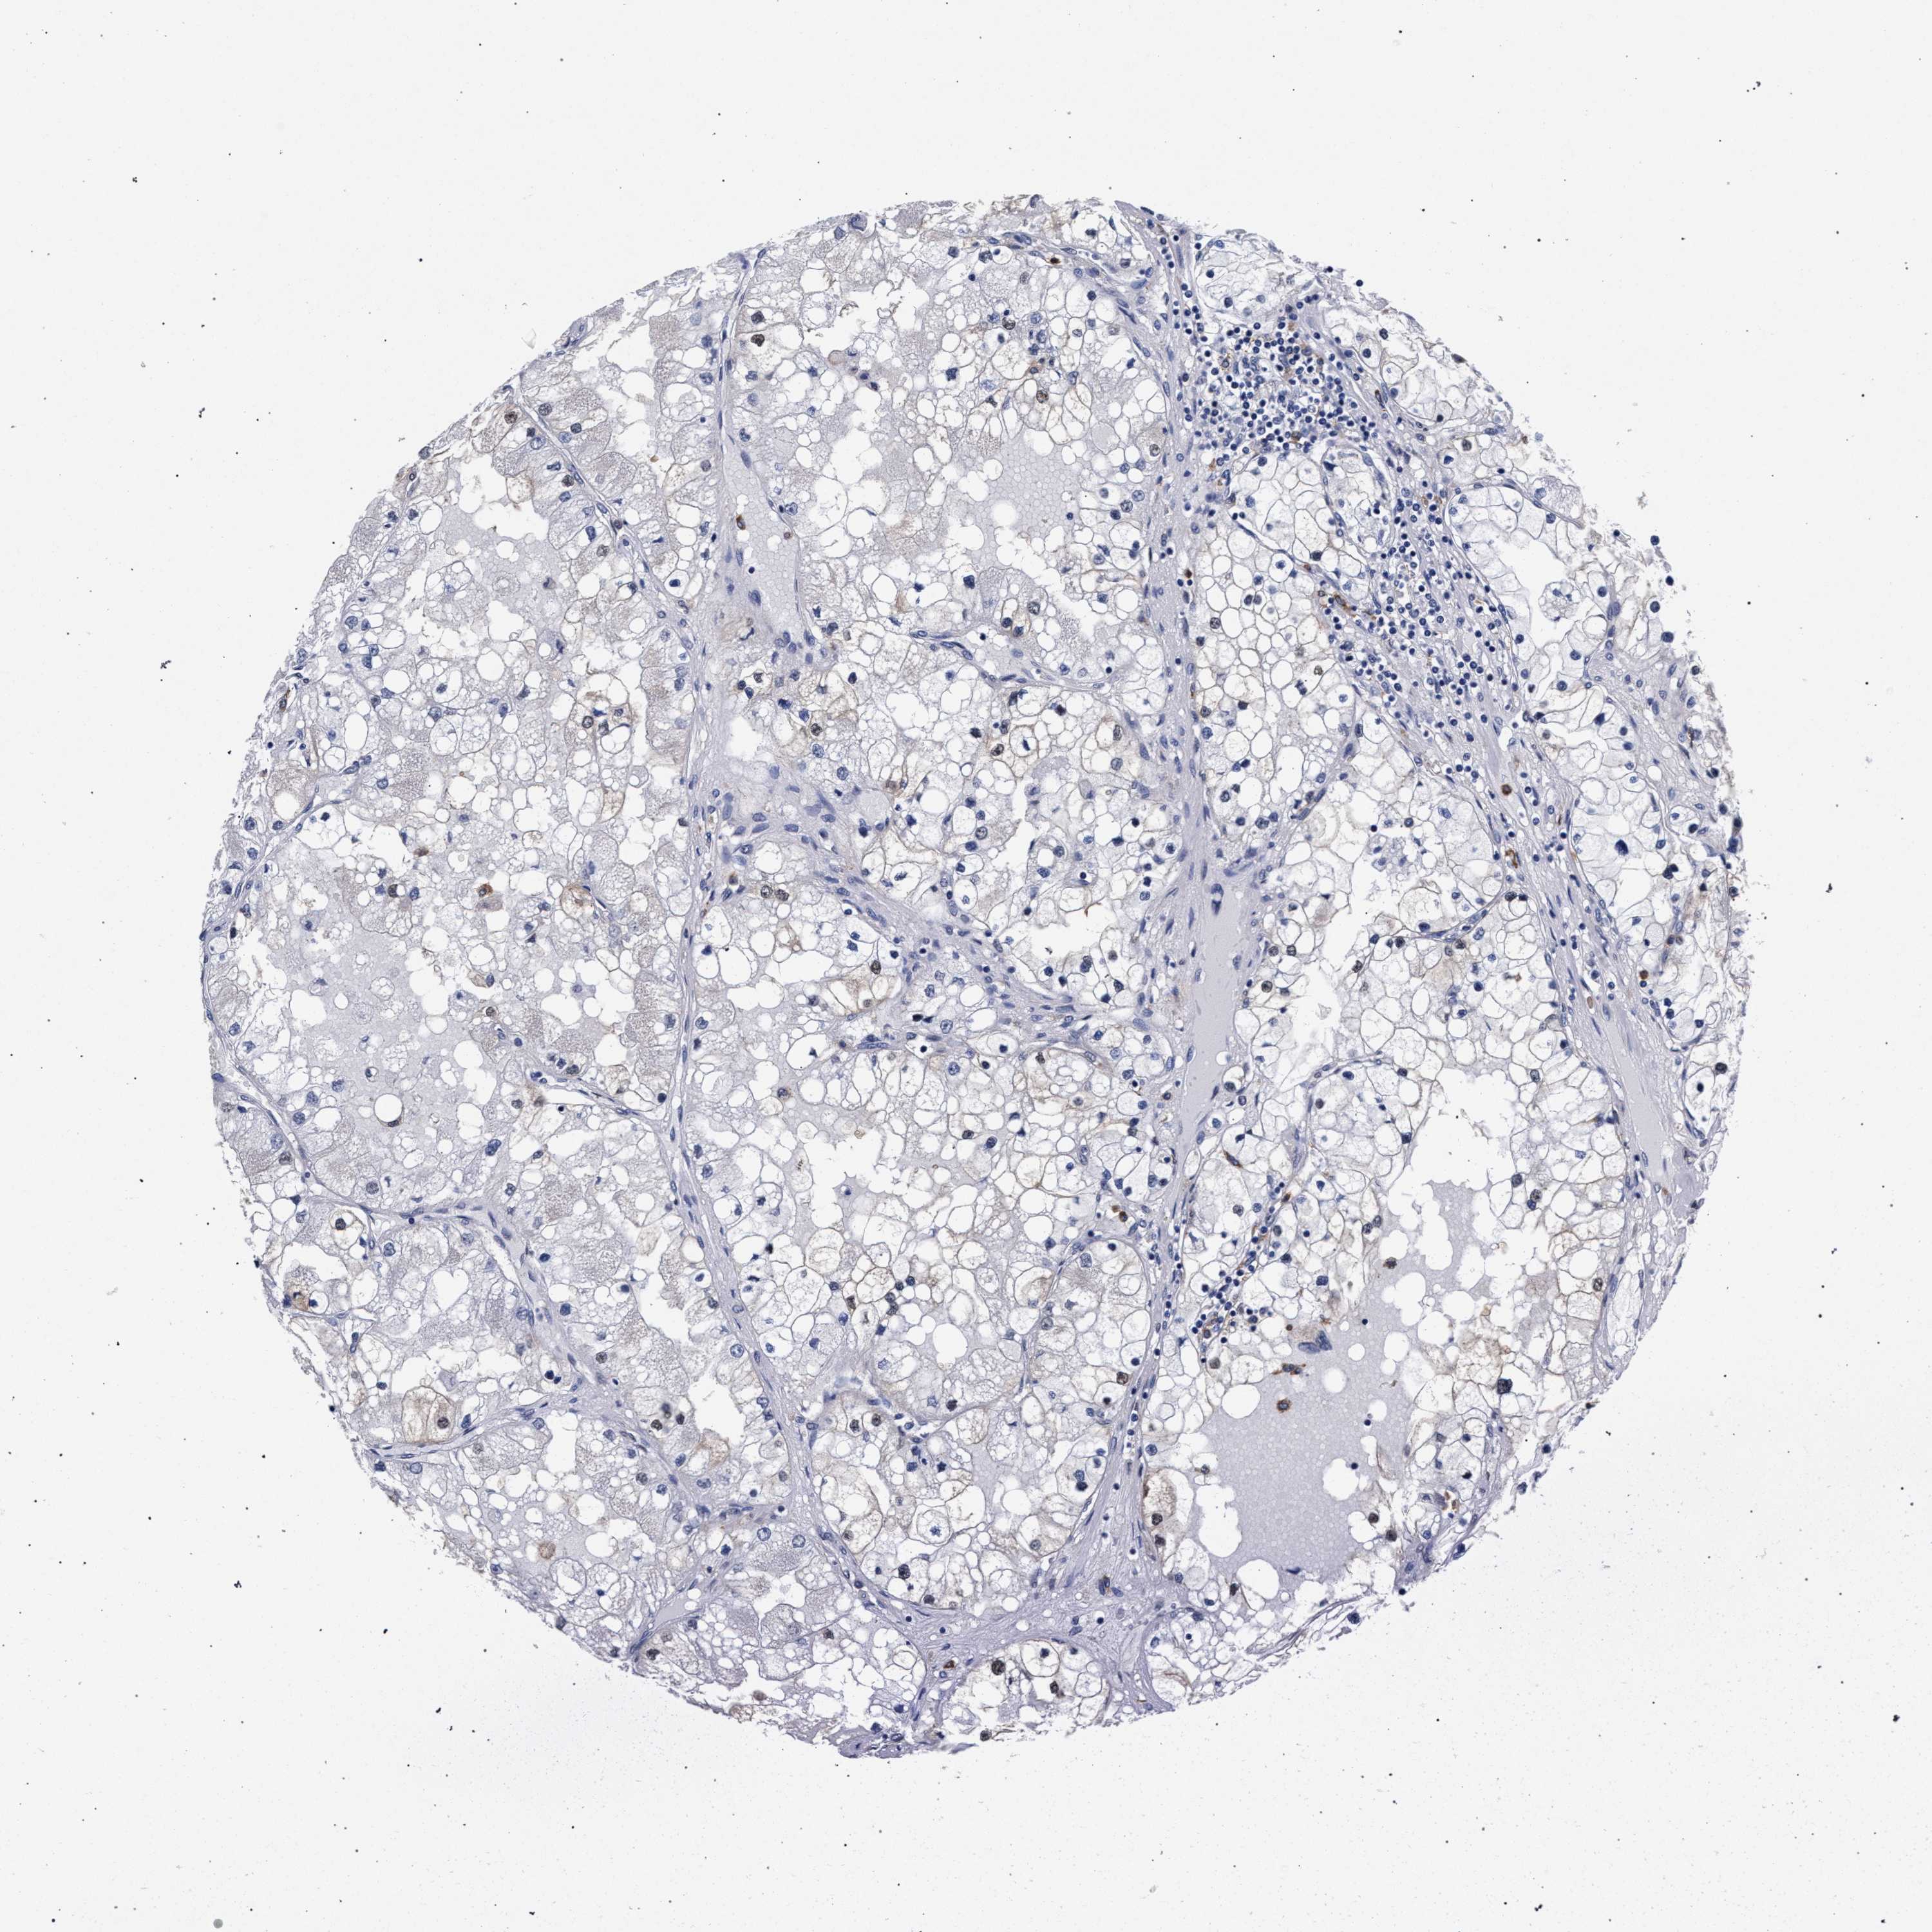

KIDNEY RENAL CLEAR CELL CARCINOMA (VALIDATION) - Interactive survival scatter ploti

The Survival Scatter plot shows the clinical status (i.e. dead or alive) for all individuals in the patient cohort, based on the same data that underlies the corresponding Kaplan-Meier plots. Patients that are alive at last time for follow-up are shown in blue and patients who have died during the study are shown in red.

The x-axis shows the expression levels (FPKM) of the investigated gene in the tumor tissue at the time of diagnosis. The y-axis shows the follow-up time after diagnosis (years). Both axes are complimented with kernel density curves demonstrating the data density over the axes. The top density plot shows the expression levels (FPKM) distribution among dead (red) and alive patients (blue). The right density plot shows the data density of the survived years of dead patients with high and low expression levels respectively, stratified using the cutoff indicated by the vertical dashed line through the Survival Scatter plot. This cutoff is automatically defined based on the FPKM cutoff that minimizes the p-score. The cutoff can be changed by dragging the vertical line or by entering a cutoff value in the square labeled "Current cut-off".

Under the Survival Scatter plot the p-score landscape (black curve; left axis) is shown together with dead median separation (red curve; right axis). Dead median separation is the difference in median mRNA expression between patients who have died with high and low expression, respectively. It is calculated as follows: median FPKM expression of dead patients with high expression - median FPKM expression of dead patients with low expression. This is intended to aid the user in visually exploring custom cutoffs and the associated p-scores and dead median separation.

Individual patient data is displayed and can be filtered by clicking on one or more of the category buttons on the top of the page. Categories describing expression level and patient information include: high, low, alive, dead, female, male and tumor stages. The scale of the x-axis can be toggled between linear and log-scale by clicking on the "x log" button. Mouse-over function shows TCGA ID, patient information and mRNA expression (FPKM) for each patient.

& Survival analysisi

Kaplan-Meier plots summarize results from analysis of correlation between mRNA expression level and patient survival. Patients were divided based on level of expression into one of the two groups "low" (under cut off) or "high" (over cut off). X-axis shows time for survival (years) and y-axis shows the probability of survival, where 1.0 corresponds to 100 percent.

ZNF462 is validated prognostic, high expression is favorable in Kidney Renal Clear Cell Carcinoma (validation)

: 5.39

Average pTPM 7.1

Number of samples 100